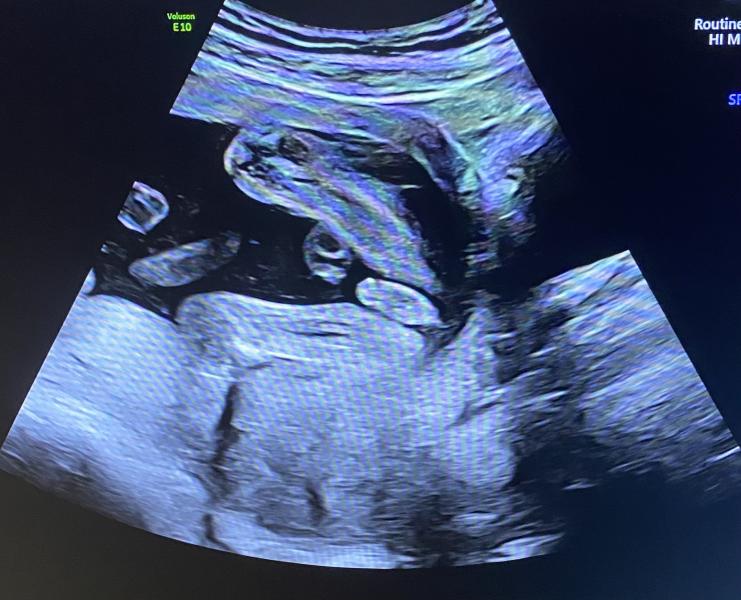

МАЛЬЧИК

Муж счастлив, осталось дочери сказать,что сестра все-таки отменяется😁

С дочкой все были уверены,что мальчик, а я топила за девочку.

С сыном все сейчас уверены,что девочка, а я даже не сомневалась,что мальчик.